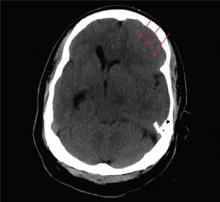

You are called to the emergency department (ED) in reference to a patient who was sent there by radiology with a reported “brain mass” noted on imaging. During further investigation in the ED, the patient, who is in his 50s, stated that he has had headaches for the past several weeks; he consulted his primary care provider, who ordered outpatient MRI of the brain—the test that ultimately led to his arrival in the ED. Since the MRI results were not immediately available for review, the ED staff obtained noncontrast CT of the head. The ED provider notes that it “looks like there is something there causing significant mass effect and shift.” When you arrive to see the patient, you note that he is awake, alert, and oriented times three. His Glasgow Coma Scale score is 15, and his vitals signs are normal. He states he has a mild headache, rating it a 3 out of 10 on a pain scale. His only other complaint is mild right-sided weakness, which he has noticed in the past week or so. Clinically, the strength in his right upper and lower extremities is good. His medical history is significant for prostate cancer and hypertension. A single cut from the CT of his head is shown. What is your impression?

The image shows obvious mass effect throughout the left hemisphere. On close examination, there is evidence of an isodense subdural collection within the left frontoparietal region. This is causing a left-to-right shift of almost 11 mm.

This finding is most likely a subacute subdural hematoma, probably seven to 14 days old. Further questioning reveals that the patient had fallen in the shower approximately two weeks prior and hit his head. The patient was admitted for observation and subsequently underwent a craniotomy for evacuation of the subdural hematoma.